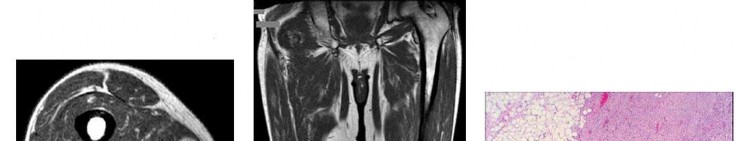

A 15-year-old male presents with deep knee pain awakening him at night. Radiographs show a permeative destructive lesion in the distal femoral metaphysis with a 'sunburst' periosteal reaction and Codman's triangle.

Biopsy confirms high-grade conventional osteosarcoma. What is the most critical prognostic factor for long-term overall survival in this patient?

Explanation

For localized high-grade osteosarcoma, the most important prognostic indicator is the histologic response to neoadjuvant chemotherapy. This is evaluated during the definitive resection. A 'good response' is typically defined as greater than 90% or 99% tumor necrosis. Patients who achieve this level of necrosis have a significantly improved disease-free and overall survival rate compared to 'poor responders' who have extensive viable tumor cells remaining.